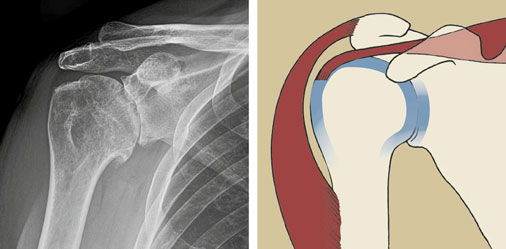

Das Schultergelenk ist ein Kugelgelenk mit einer Gelenkpfanne am Schulterblatt und einer Gelenkkugel am Oberarm. Der Gelenkknorpel bedeckt sowohl die Gelenkpfanne als auch die Gelenkkugel und ermöglicht ein optimales Gleiten der Gelenkflächen. Die Gelenkpfanne der Schulter ist nur flach ausgebildet und bedeckt lediglich einen geringen Teil der Gelenkkugel. Dadurch wird dem Schultergelenk seine große Beweglichkeit ermöglicht. Voraussetzung, dass dieses Gelenk gut funktioniert, ist deshalb ein intakter Weichteilmantel. Dazu gehören sowohl die Gelenkkapsel mit den darin enthaltenen Bändern als auch Sehnen und die umgebende Muskulatur. Die Muskulatur besteht aus einer inneren Schicht, der Rotatorenmanschette, welche dem Gelenk eine aktive Stabilität verleiht, und einer äußeren Schicht – dem kräftigen Deltoidmuskel. Die sind für das aktive Anheben des Armes verantwortlich.

Verschiedene Erkrankungen können zu einer Zerstörung der Gelenkflächen führen. Das Endstadium dieses Prozesses ist die Arthrose des Schultergelenkes (Omarthrose). Dabei wird der Knorpel abgenützt, und das Gelenk verliert durch knöcherne Anbauten (Osteophyten) zunehmend seine Passform. Weitere Ursachen für eine Gelenkzerstörung sind entzündliche Erkrankungen wie die chronische Polyarthritis, Durchblutungsstörung des Oberarmkopfes (Humeruskopfnekrose), Unfallfolgen, eine chronische Instabilität oder ausgedehnte Sehnenrisse der Rotatorenmanschette.

Fortgeschrittene Arthrose der Schulter. Die Gelenkflächen sind zerstört.